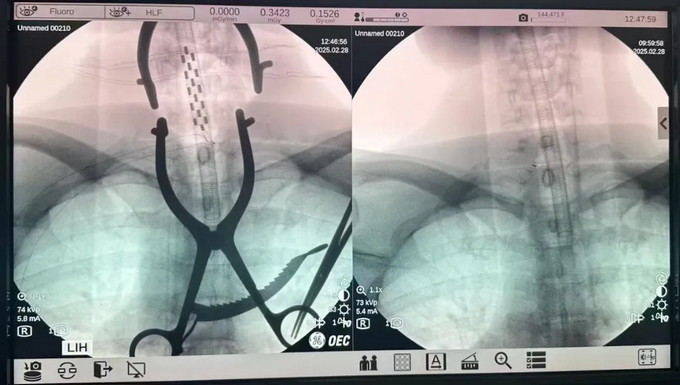

近日,福建中醫(yī)藥大學(xué)附屬人民醫(yī)院神經(jīng)外科成功開展了一臺(tái)SCS(脊髓電刺激)手術(shù),標(biāo)志著我院在功能神經(jīng)外科領(lǐng)域取得了重要突破。這一手術(shù)的成功實(shí)施,為偏癱、肢體痙攣、昏迷促醒、頑固性疼痛、糖尿病足等患者帶來了福音。

SCS手術(shù)作為功能神經(jīng)外科的重要手術(shù)之一,主要用于治療偏癱、肢體痙攣、昏迷促醒、頑固性疼痛、糖尿病足等病癥,通過精準(zhǔn)的神經(jīng)刺激,幫助患者改善肢體功能,提高生活質(zhì)量。與此同時(shí),針對(duì)外傷、腦出血、腦卒中后昏迷的患者,通過特定的神經(jīng)調(diào)控技術(shù),促進(jìn)患者蘇醒,讓他們重獲新生的希望。

此次SCS手術(shù)的順利完成,不僅展示了福建中醫(yī)藥大學(xué)附屬人民醫(yī)院神經(jīng)外科團(tuán)隊(duì)精湛的醫(yī)術(shù)和豐富的經(jīng)驗(yàn),更體現(xiàn)了醫(yī)院在神經(jīng)外科領(lǐng)域的先進(jìn)技術(shù)水平,也為更多患者帶來了康復(fù)的希望。